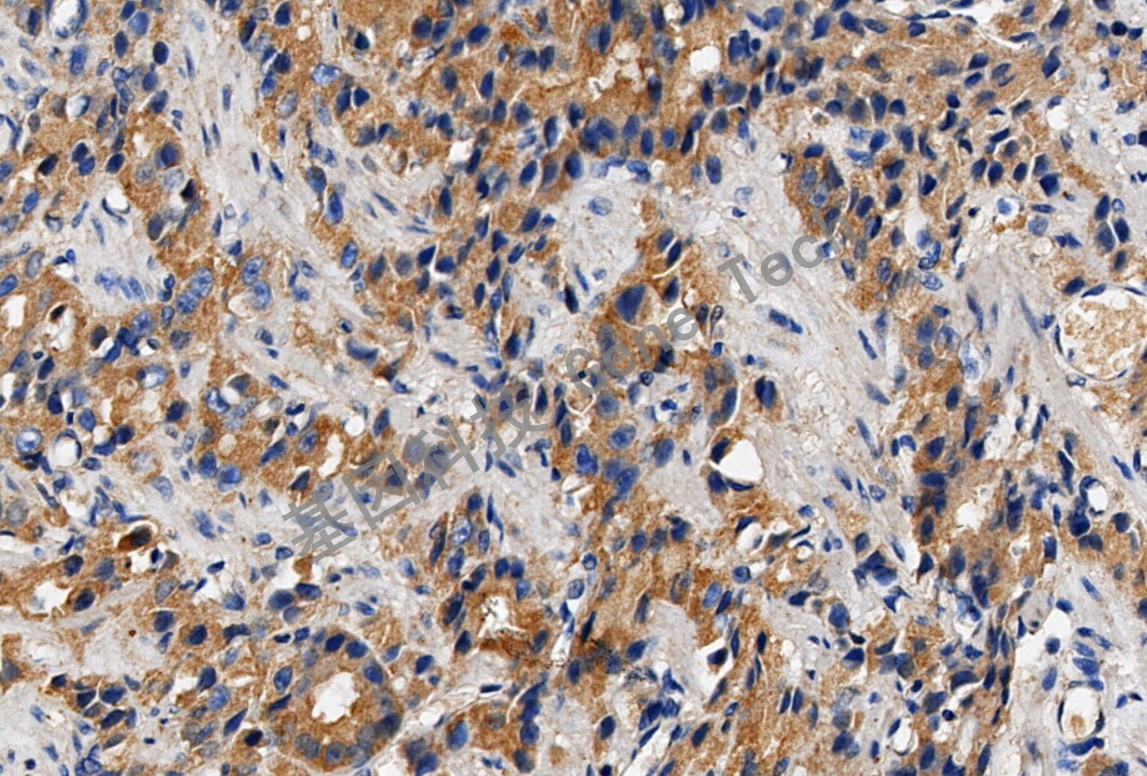

| 克隆號(hào):VG1 | 種屬:鼠 | 適用染色系統(tǒng):GTvisionTM |

| 預(yù)處理:高pH熱修復(fù) | 陽(yáng)性部位:細(xì)胞漿 | 陽(yáng)性對(duì)照:肝癌/血管肉瘤 |

| 肝癌石蠟切片,用 VEGF(GT2170)染色,細(xì)胞漿陽(yáng)性,DAB 顯色。 | ||